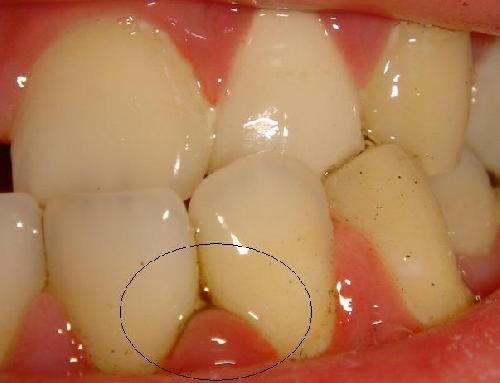

如图, 我的症状是牙龈炎还是牙周炎 或者其他口腔问题.

以下是我的牙齿解图

这个部位的牙龈乳头有炎症,可用消炎类药物.局部可涂抹碘甘油不过国外不一定有这种药物.剔牙时尽量别损伤牙龈.别的部位牙龈问题不太大.祝你好运!